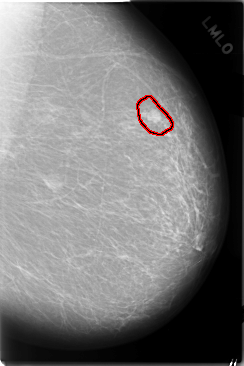

FILE: C_0025_1.LEFT_MLO.OVERLAY

TOTAL_ABNORMALITIES 1

ABNORMALITY 1

LESION_TYPE MASS SHAPE OVAL MARGINS CIRCUMSCRIBED

ASSESSMENT 4

SUBTLETY 5

PATHOLOGY MALIGNANT

TOTAL_OUTLINES 1

BOUNDARY